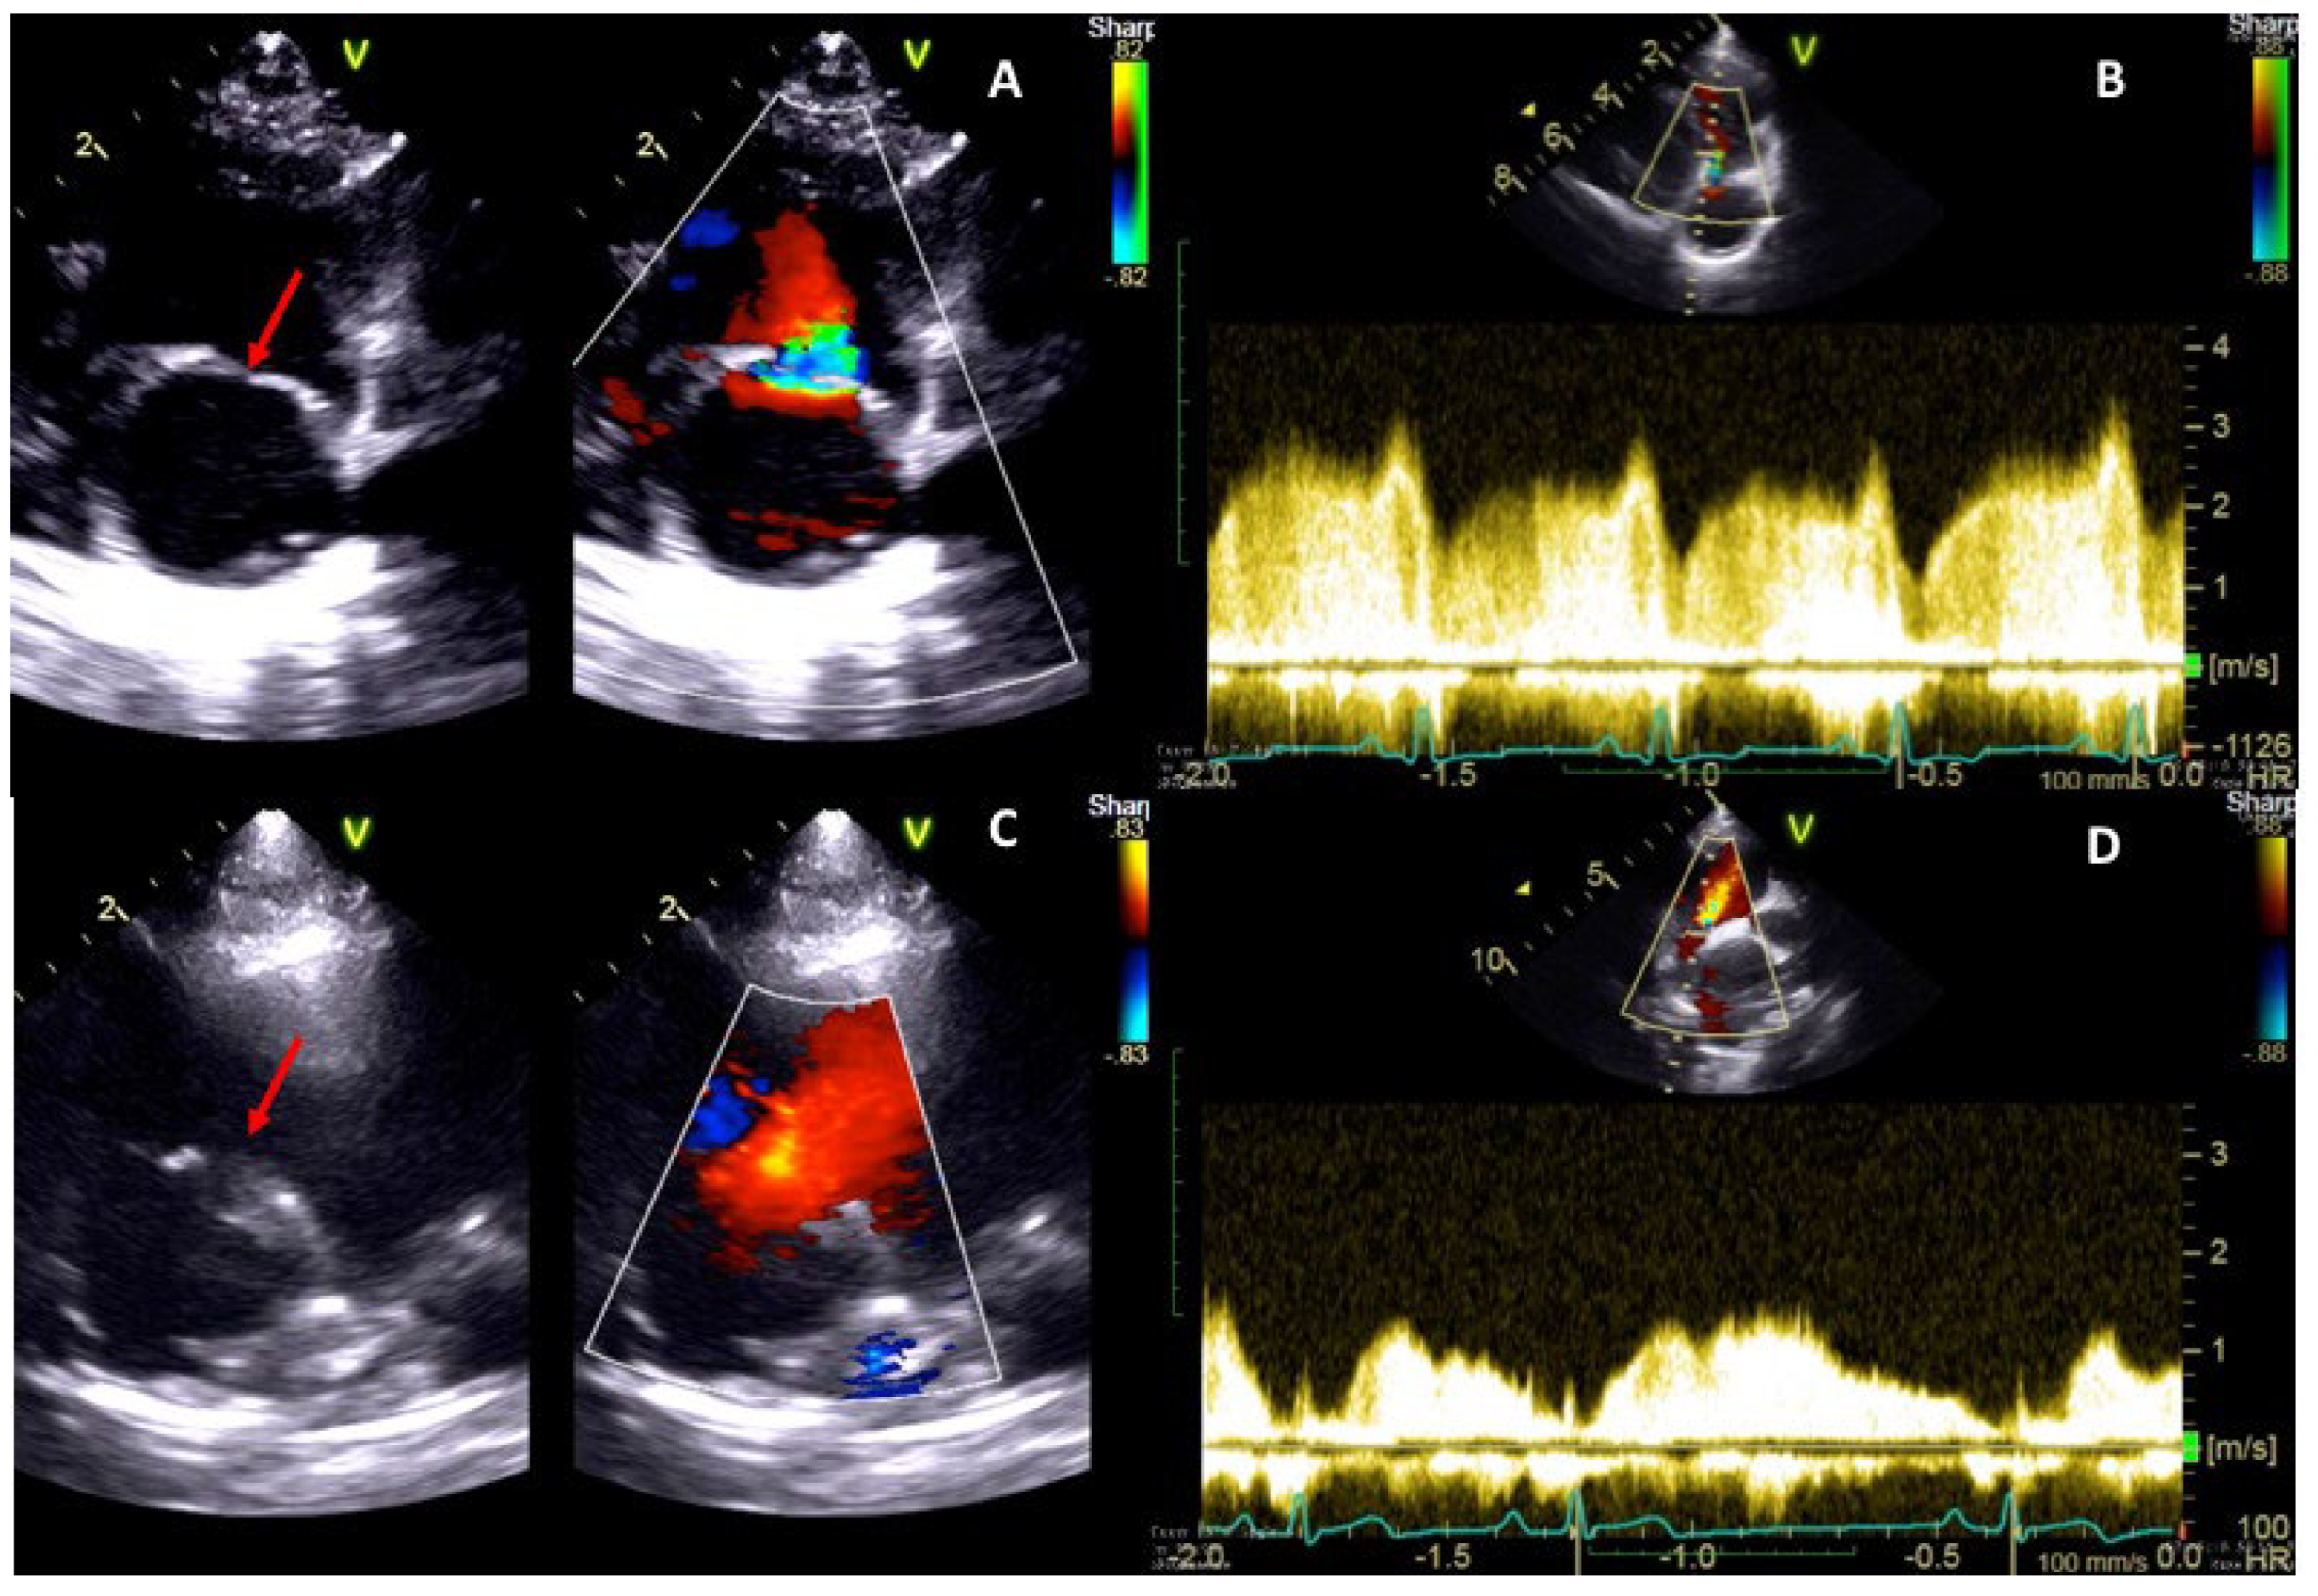

2.1. Case 1

2.2. Case 2